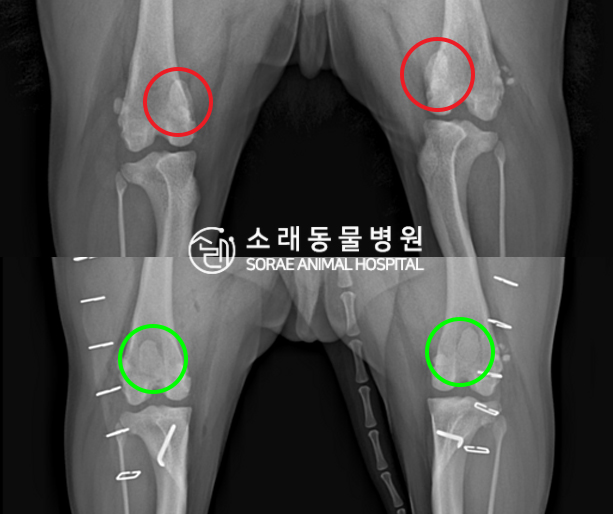

수술전과 수술후에 촬영한 콩국이의 슬개골

방사선 사진입니다. 나란히 놓고 비교해보니

슬개골의 위치에 확연한 차이가 있는 것을

확인해 볼 수 있는데요. 내측으로 탈구되어 있던

슬개골이 원래 제자리인 활차구에 예쁘게

자리 잡고 있는 모습을 확인할 수 있었습니다.